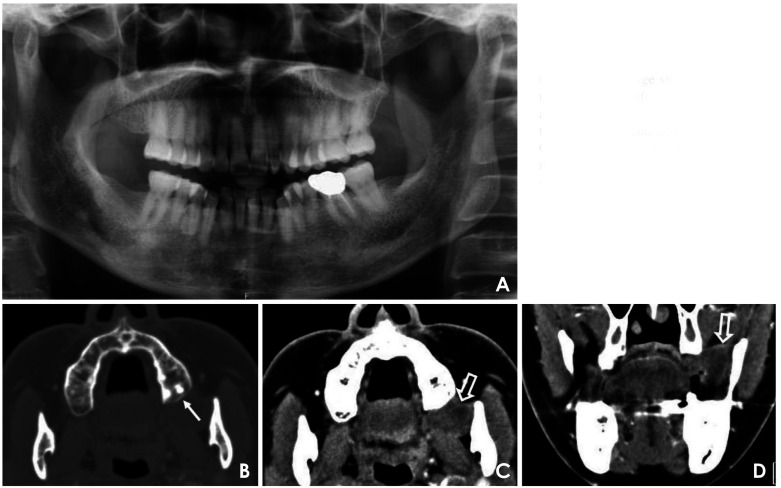

Basal cell adenocarcinoma, considered to be the malignant counterpart of basal cell adenoma, is a rare, low-grade malignant tumor of the salivary glands, accounting for 1-2% of salivary gland malignancies. It predominantly affects the parotid gland, while involvement of the minor salivary glands is exceptionally rare. This report presented a case of basal cell adenocarcinoma involving the left retromolar trigone in a 54-year-old woman. The initial provisional diagnosis suggested a benign or low-grade malignant salivary tumor. Advanced magnetic resonance imaging techniques, including diffusion-weighted imaging and apparent diffusion coefficient analysis, aided in the preoperative prediction of malignancy, and an incisional biopsy confirmed the diagnosis of basal cell adenocarcinoma. This case underscored the challenge of distinguishing basal cell adenocarcinoma from benign salivary tumors, as clinical and imaging features often overlap. Surgical excision remains the primary treatment, yielding favorable outcomes; however, long-term follow-up is crucial due to the risk of recurrence.

Abstract Image